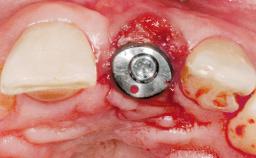

Immediate Flapless Placement of an Implant in a Maxillary Right Lateral Incisor Site

This 43-year-old male patient, a non-smoker, came to our practice because of a fracture of tooth 12 caused by a bicycle accident. Due to the combined para- and infrabony crown and root fracture, tooth extraction, and subsequent implant placement were suggested to the patient as the therapy of choice. The patient had high esthetic expectations with regard to the treatment outcome and asked for an immediate fixed provisional restoration. His individual esthetic risk profile summed up to a medium esthetic risk.

Placement Protocol Immediate implant placement

Tooth Site Maxillary incisor or canine

Socket Morphology Single-root socket

Socket Integrity Sufficient, with intact bone walls